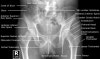

Pelvic X-ray의 Anatomy와 Positioning

- A/P Pelvis

Demonstrates: Acetabulum, pelvic ring, femoral neck, femoral heads

Helpful for: Acetabular fx, Pelvic ring injury, Femoral neck fx, IT fx, hip arthritis, THA, AVN

Position: Supine with feet interally rotated 15°. Center cassette midway between ASIS and pubic symphysis. If feet externally rotated lesser trochanter is visible.

Beam directed perpendicular to plate.

Adult Pelvis AP View(Male)

Adult Pelvis AP View(Female)